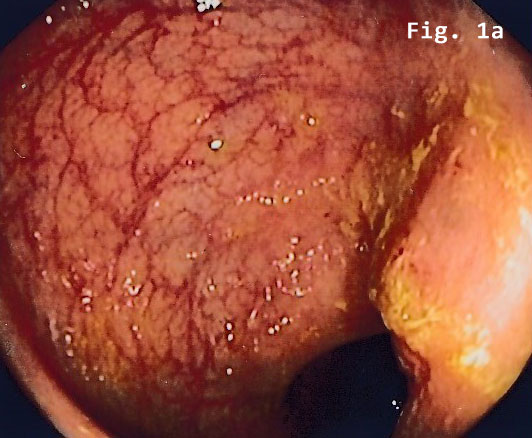

Colonoscopy revealed a semi-circular polypoid lesion in the sigmoid colon suggesting malig-nancy [Figure 1].

![Endometriosis infiltrating the sigmoid colon</br> [May 2017]](http://s834315022.websitehome.co.uk/wp-content/uploads/2020/11/cotm_may2017_fig1a.jpg)

![Endometriosis infiltrating the sigmoid colon</br> [May 2017]](http://s834315022.websitehome.co.uk/wp-content/uploads/2020/11/cotm_may2017_fig1b.jpg)